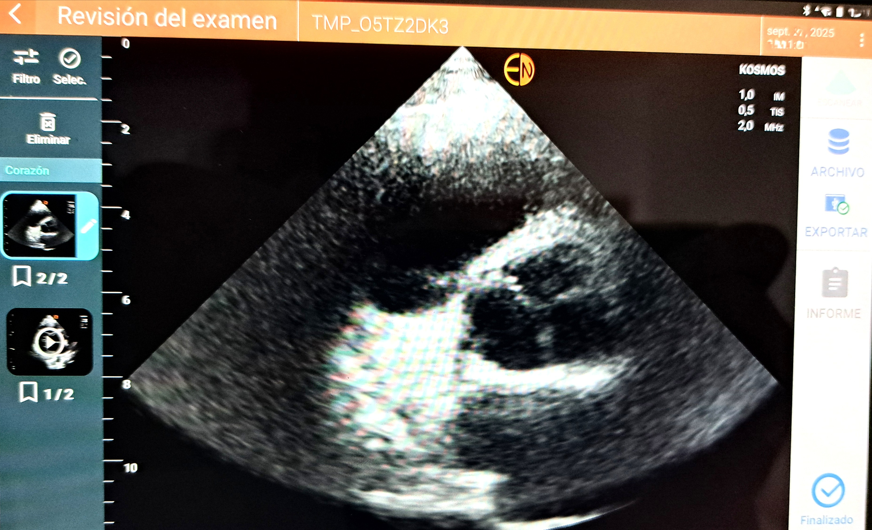

Se realizó ecocardiografía con equipo portátil KOSMOS visualizándose válvula aórtica trivalva. No se evidenciaron alteraciones estructurales.

Paciente con válvula aórtica trivalva. Pendiente de su valoración en consulta especializada para confirmar el diagnóstico.